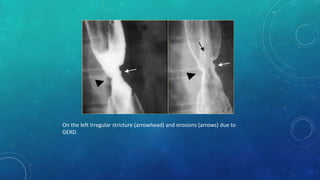

On the left Irregular stricture (arrowhead) and erosions (arrows) due to

GERD.